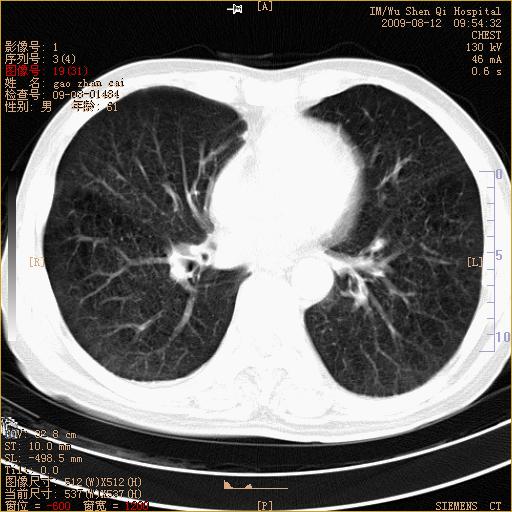

标题: CT21567:咳嗽,咳痰,发热半月余 [打印本页]

标题: CT21567:咳嗽,咳痰,发热半月余

1、右上肺继发性肺结核合并感染;2、肺气肿。

考虑支气管囊肿合并感染.

右肺间质纤维化右肺间质性肺炎

右肺上叶干酪性肺炎

右肺弥漫性间质性改变

考虑右肺间质性肺炎并右侧胸膜炎可能性大。

右上肺干酪性肺炎,肺气肿

考虑右肺支扩并感染可能,结核不除外,结核生化检查看看。

右肺门区占位待排(图片没有传完)

右肺间质性肺炎,肺气肿

考虑右肺结核, 右肺间质性改变,肺气肿。

支持右肺间质性肺炎。

右肺上叶支扩并感染,肺间质纤维化。

1)右肺上叶感染性病变;建议抗炎治疗后复查。2)肺气肿。

右肺上叶支扩并感染,肺间质纤维化,肺气肿,右肺门淋巴结肿大。建议抗炎治疗后复查。

支扩合并感染